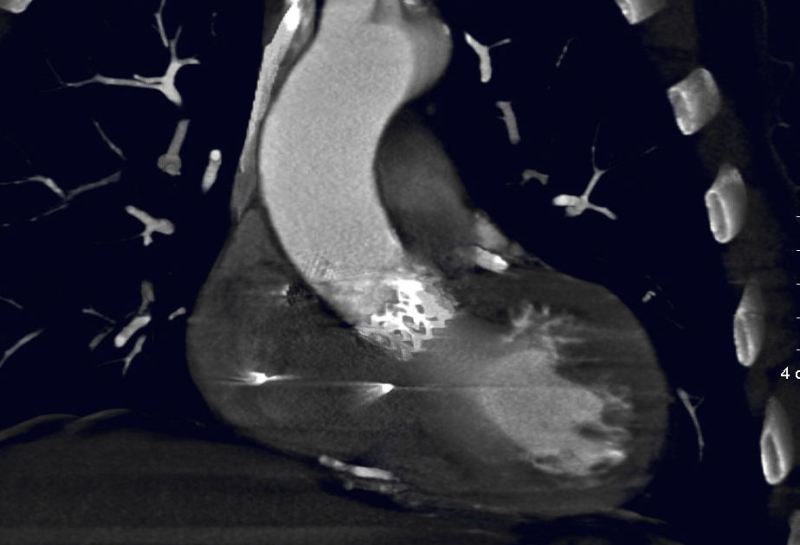

Imagen4

Figura 3. Imagen de TAC mostrando la TAVI en su posición habitual.